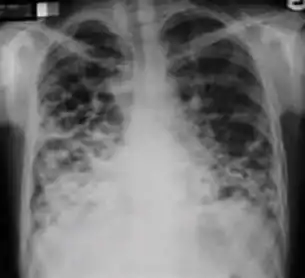

7. Other - Any other finding suggestive of active TB, such as miliary TB. Miliary findings are nodules of millet size (1 to 2 millimeters) distributed throughout the parenchyma.

Chest x-ray showing coarse reticulonodular densities on the lower right lung of post-primary pulmonary TB.